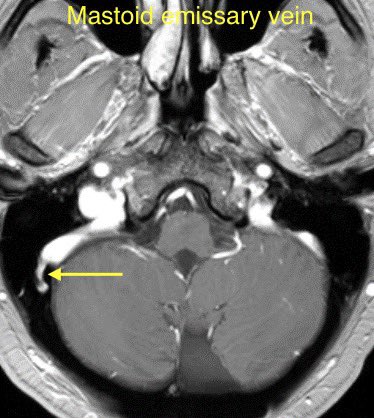

🔷EMISSARY VEIN ANOMALIES AND VARIANTS

1️⃣Mastoid emissary veins

🔹Mastoid emissary veins (connect posterior auricular or occipital veins with the sigmoid sinus). These are common & usually incidental findings though have been associated with PT